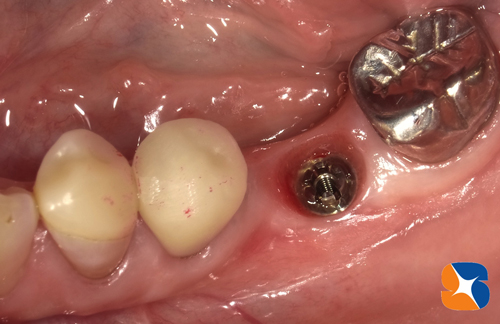

〈手術から3ヶ月後〉

3ヶ月過ぎから仮歯を装着します。1ヶ月間使っていた後、最終の型取りに入ります。

施術から4ヶ月後、無事にセラミックで仕上げたインプラントが完成いたしました。